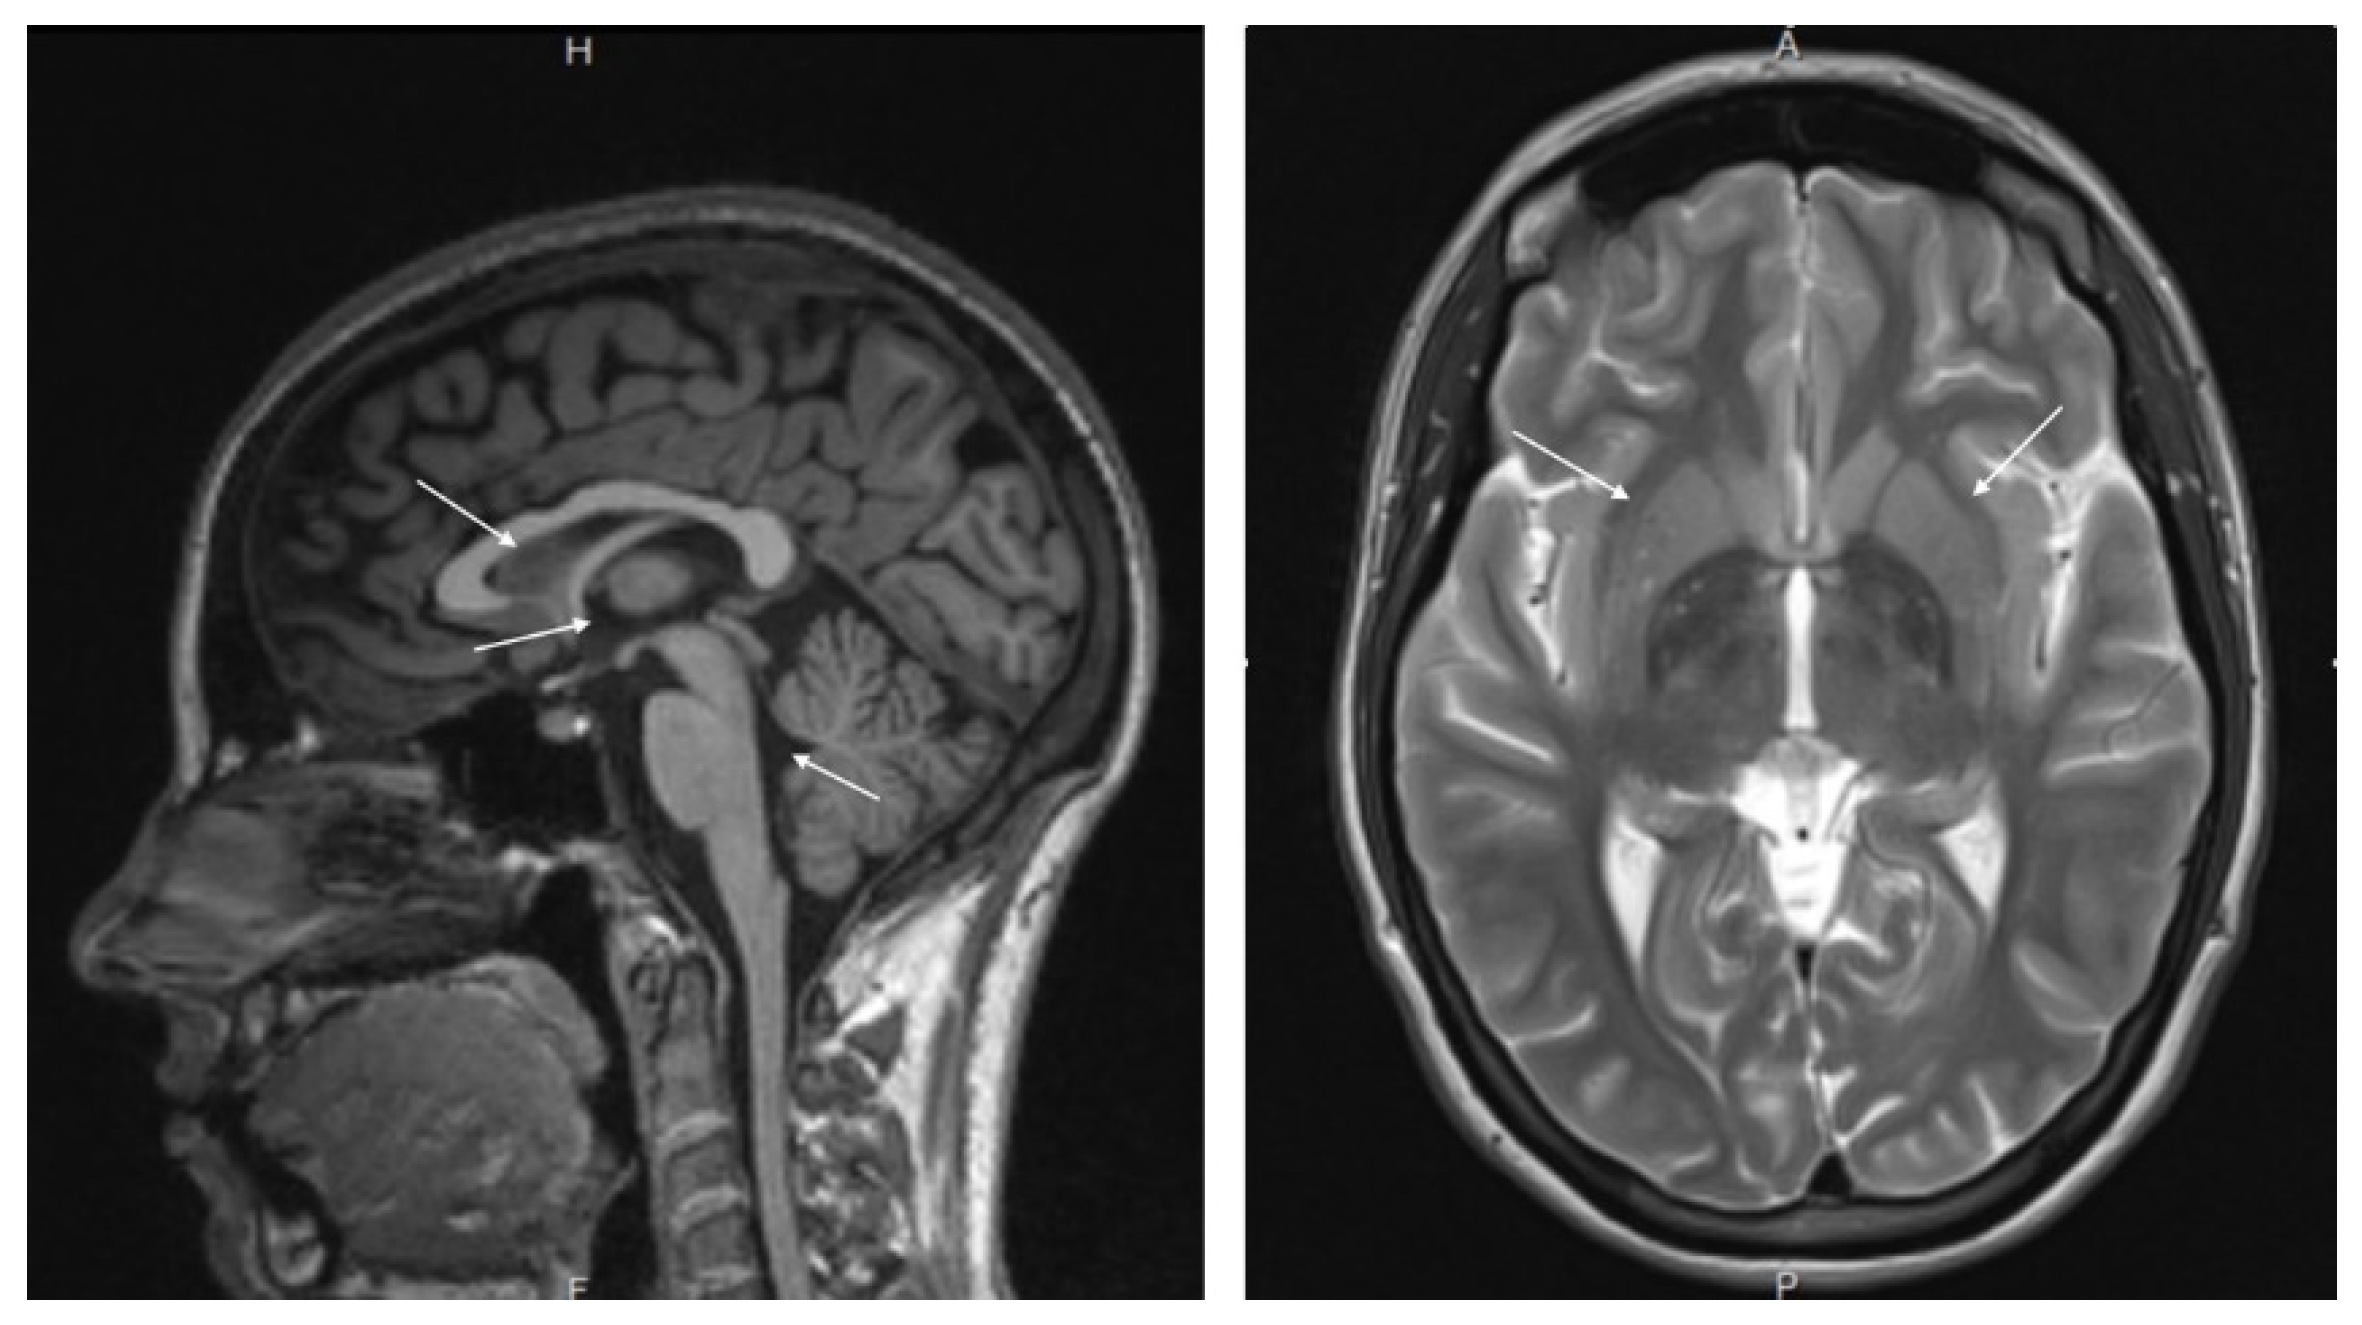

2.3.1. MRI Brain

3.1. MRI and MRA Results